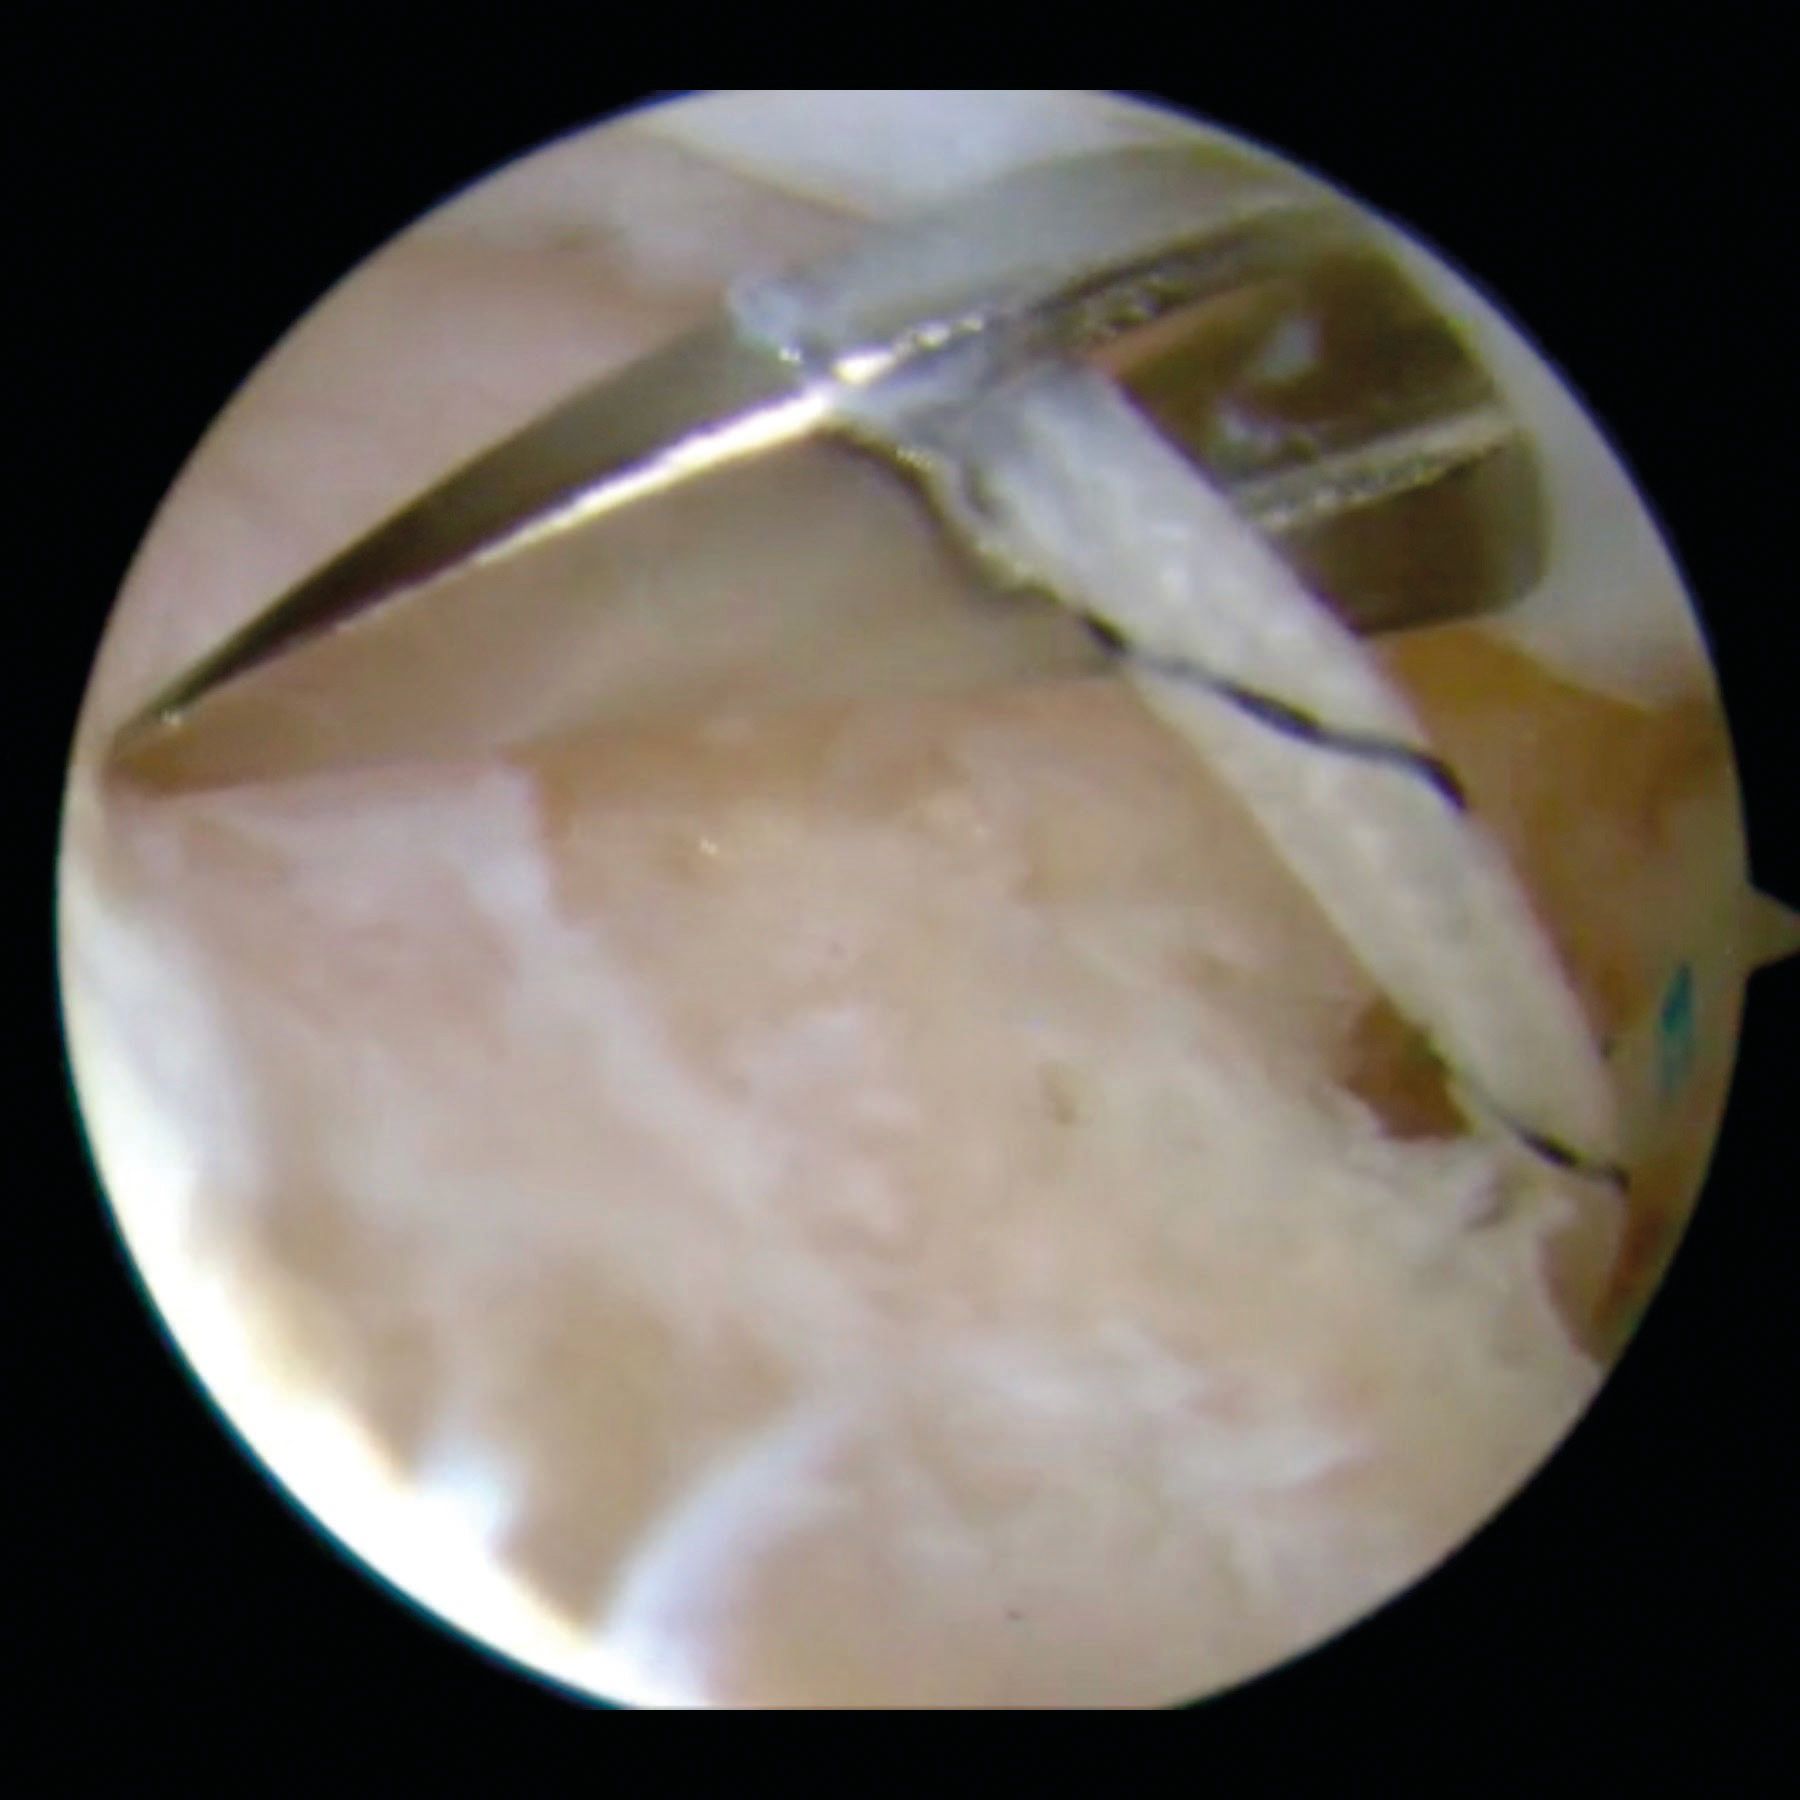

After insertion of an anchor (usually double loaded) in the bone defect, the cannula is carefully withdrawn from the posterior capsule and infraspinatus tendon but not through the deltoid. Therefore the mouth of the cannula is in the subdeltoid space. At this stage, it is a blind procedure. This position of the cannula and the variation of its angulation allow to pass the anchor and then the penetrating grasper with the suture limbs through different part of the tendon and the capsule. Figure 4.

Once the Hill-Sachs anchors are placed and sutures passed through the infraspinatus tendon, the anterior-inferior capsulolabral repair is performed. Only after finishing the anterior procedure, the posterior humeral sutures are tied, percutaneously, through the deltoid and over the infraspinatus tendon. The mattress sutures draw the infraspinatus and the posterior capsule to the abraded bony surfaces, thus achieving a filling (remplissage) of the Hill-Sachs lesion. Figure 5.